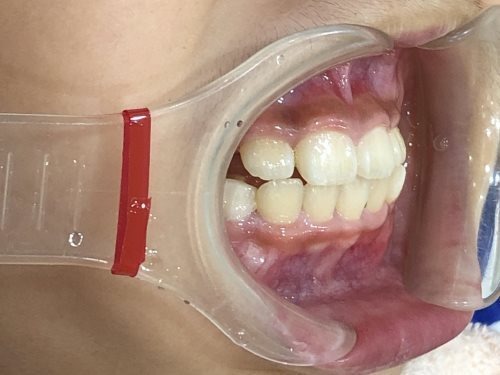

• BEFORE

症例集 インビザライン 正面

症例集 インビザライン 右横